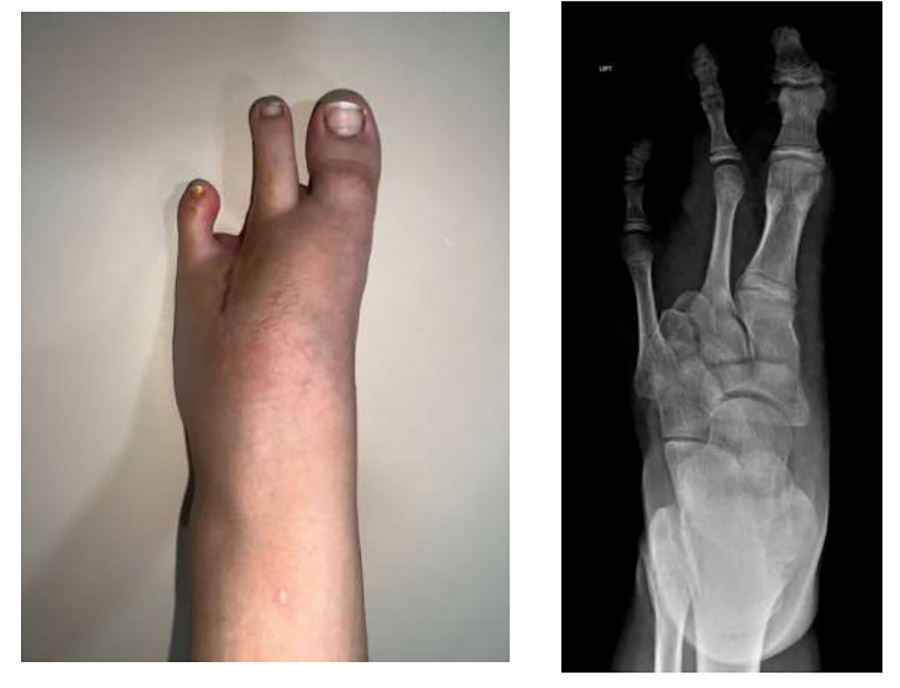

Ameliyat Sonrası: Ray amputasyon sonrası yara iyileşmesi ve röntgen görüntüsü görülmekte